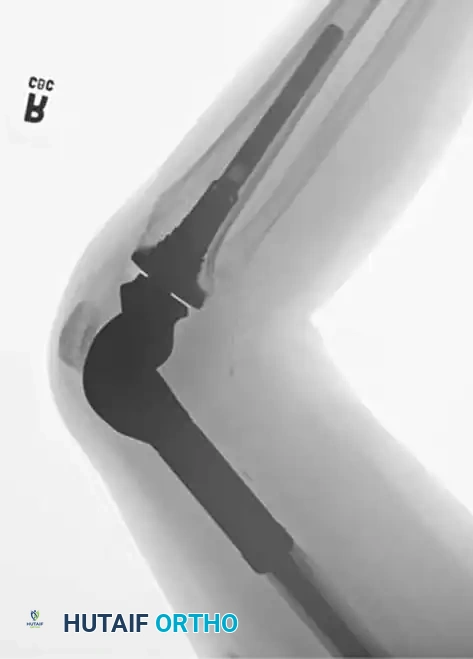

Image

Postoperative anteroposterior and lateral radiographs confirming excellent alignment and fixation of the distal femoral replacement.